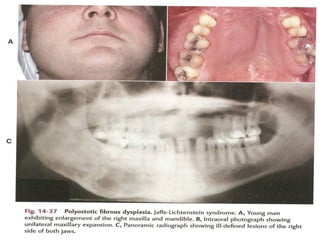

A and B, Fibrous dysplasia of the right maxilla demonstrating asymmetric

expansion. B is mirror image.